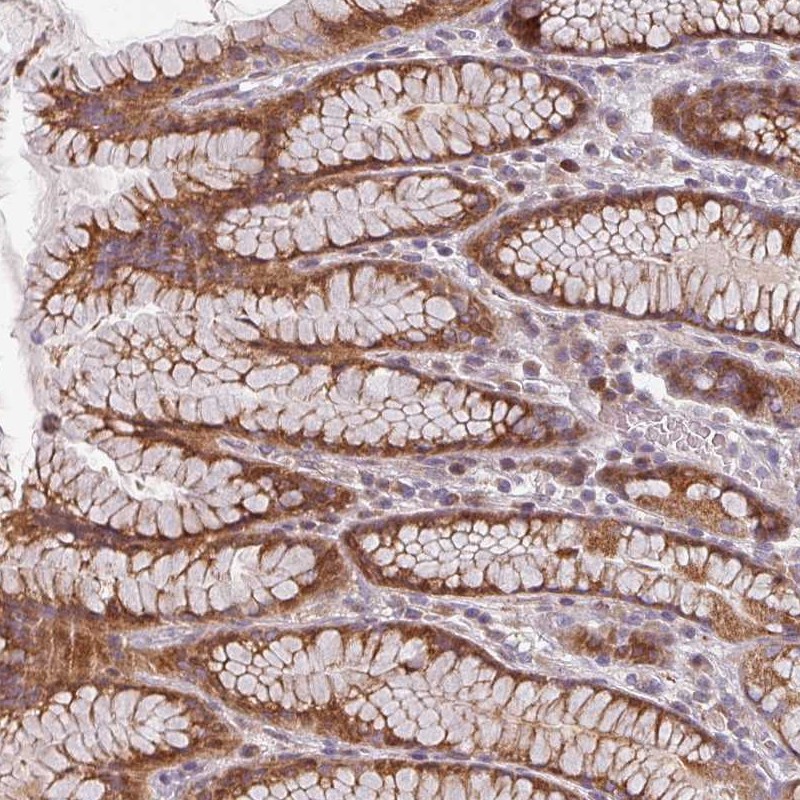

Immunohistochemical staining of human stomach, upper shows moderate cytoplasmic positivity in glandular cells.